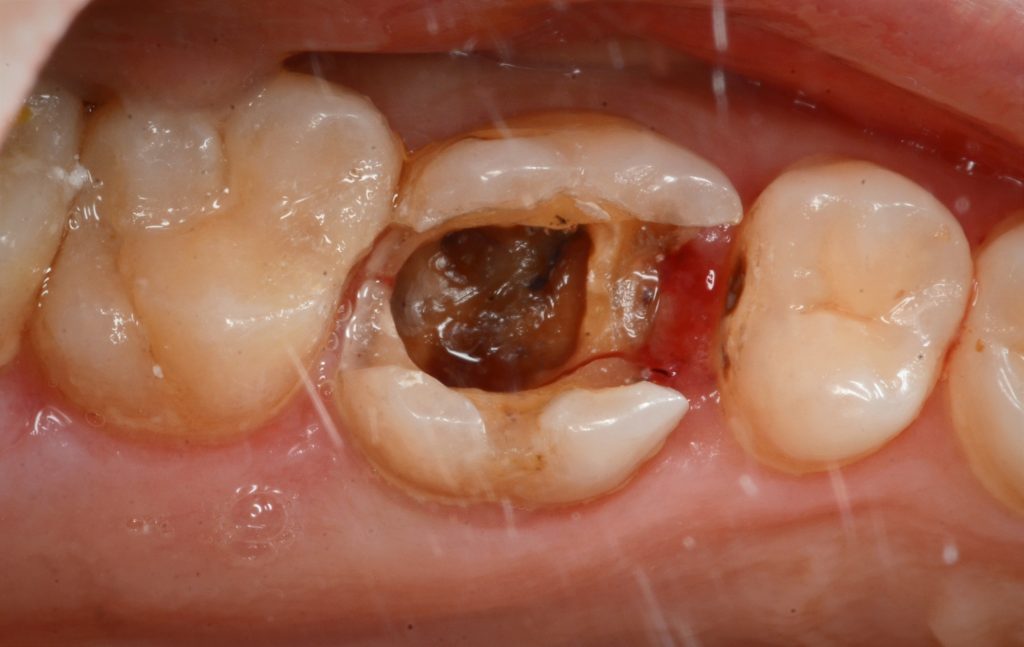

بعد إزالة الحشوة والبدء لبدء الجوتا بيرشا في الزيارة الأولى

في الزيارة الثانية لاحظنا كسر بصري في جدار الحنك (المريض في ذلك الوقت كان يعاني من الإجهاد ونير الأسنان أثناء النوم)

After first visit horizontal fracture occurred

Remove piece of fracture

Crown lengthing procedure

Isolation to build up and dme

After deep margin elevation